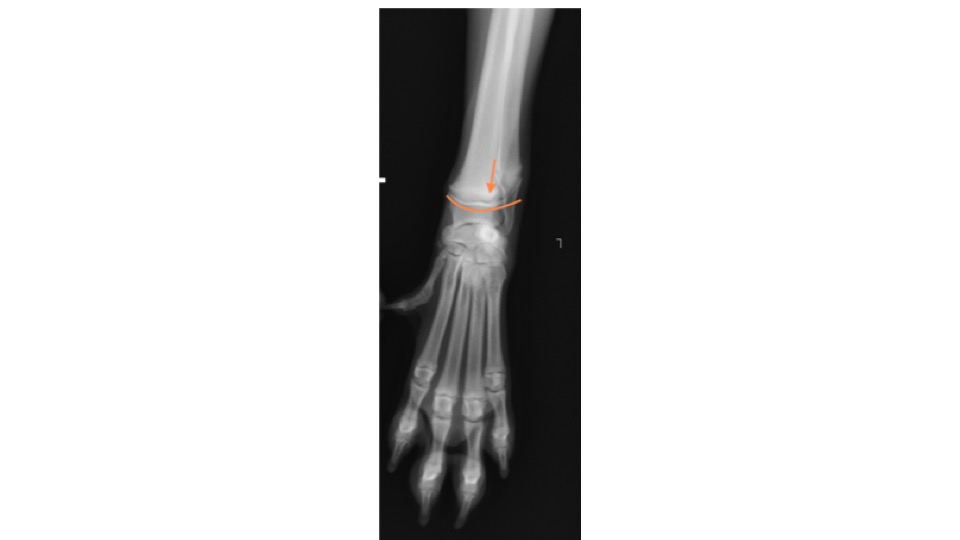

レントゲン検査を行ったところ、右手根骨のⅠ型成長板骨折が認められました。

→の部分が骨折部位になります。

この画像の曲線が、正常な成長板です。下の画像と比較してみると、わかりにくいですが骨折線が認められます。

成長板骨折は1方向だけのレントゲン画像では診断が難しいため、必ず2方向(横、正面)からの撮影を行います。